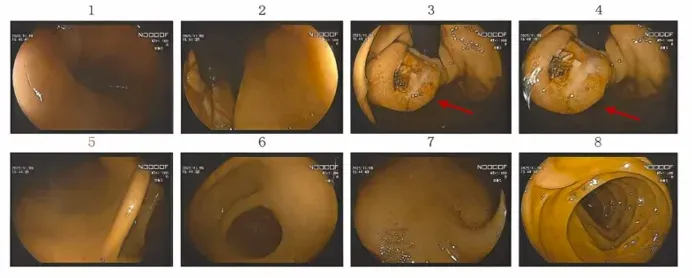

患者为38岁男性,因“反复黑便伴头晕1月”前来就诊。病程中查血红蛋白最低降至90g/L。胃镜及相关影像学检查显示:胃底贲门区可见一约4cm大小的肿物,伴有溃疡及出血。综合辅助检查考虑该患者诊断为胃间质瘤可能性大。

▲术前胃肠镜检查结果:红色标注为胃底肿物